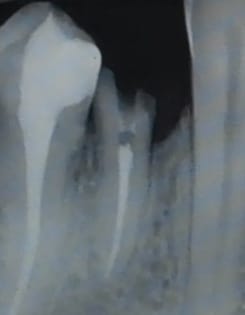

Cas ultra classique mais j'aimerais en discuter avec vous.

Ma voisine de 40 ans, adorable, en bonne santé qui a fait une pulpite sur 14 cet été ; le dentiste en urgence lui a mis un pansement pour la soulager.

J'ai fait l'endo, la préparation pour IC bientôt je ferai l'élongation coronaire en distal mais je trouve que tout cela est terriblement "mutilant"

la 14 a une ligne de faiblesse (sillon O MD, ligne de coalescence des bourgeons lors de la formation), pour moi la dent qui se fracture le plus (vu plusieurs fois même sur dent saine et dragée ou bonbon dur) et alors c'est toujours soit l'éclatement total d'emblée soit la fracture en biseau bien sous gingival.

Moi aussi je ferais une coiffe. Par contre pour l'INCO , j'en suis revenue,( cf les considerations d'Enlaye sur les INCO), ici en particulier des racines toujours plus grêles que ce qu'on aurait imaginé, des accumulations de contraintes mal réparties sur les parois, un bras de levier(partie intra osseuse/ suparo osseuse) rendu plus defavorable du fait de la nécessité d'élongation coronaire.... une meilleure "diffusion " si reconstitution compo... donc de préference si possible.

je rajoute l'onlay ne protégera pas d'un effet de coin, ce que je redoute sur cette dent là en particulier (sa morpho).

Difficile de se rendre compte sur la rétro du degré de délabrement.

L ' IC est il vraiment nécessaire ? l' élongation coronaire est elle vraiment nécessaire?

J' aurais fait également une couronne avec une préparation verticale pour être le plus conservateur possible.

Pourquoi une élongation coronaire? Tu peux faire une limite sous gingivale juxta (je dirais même légèrement supra vu la radio, mais sans certitude) osseuse.

Le reste comme les autres, selon le délabrement, soit onlay, soit RCR +couronne.